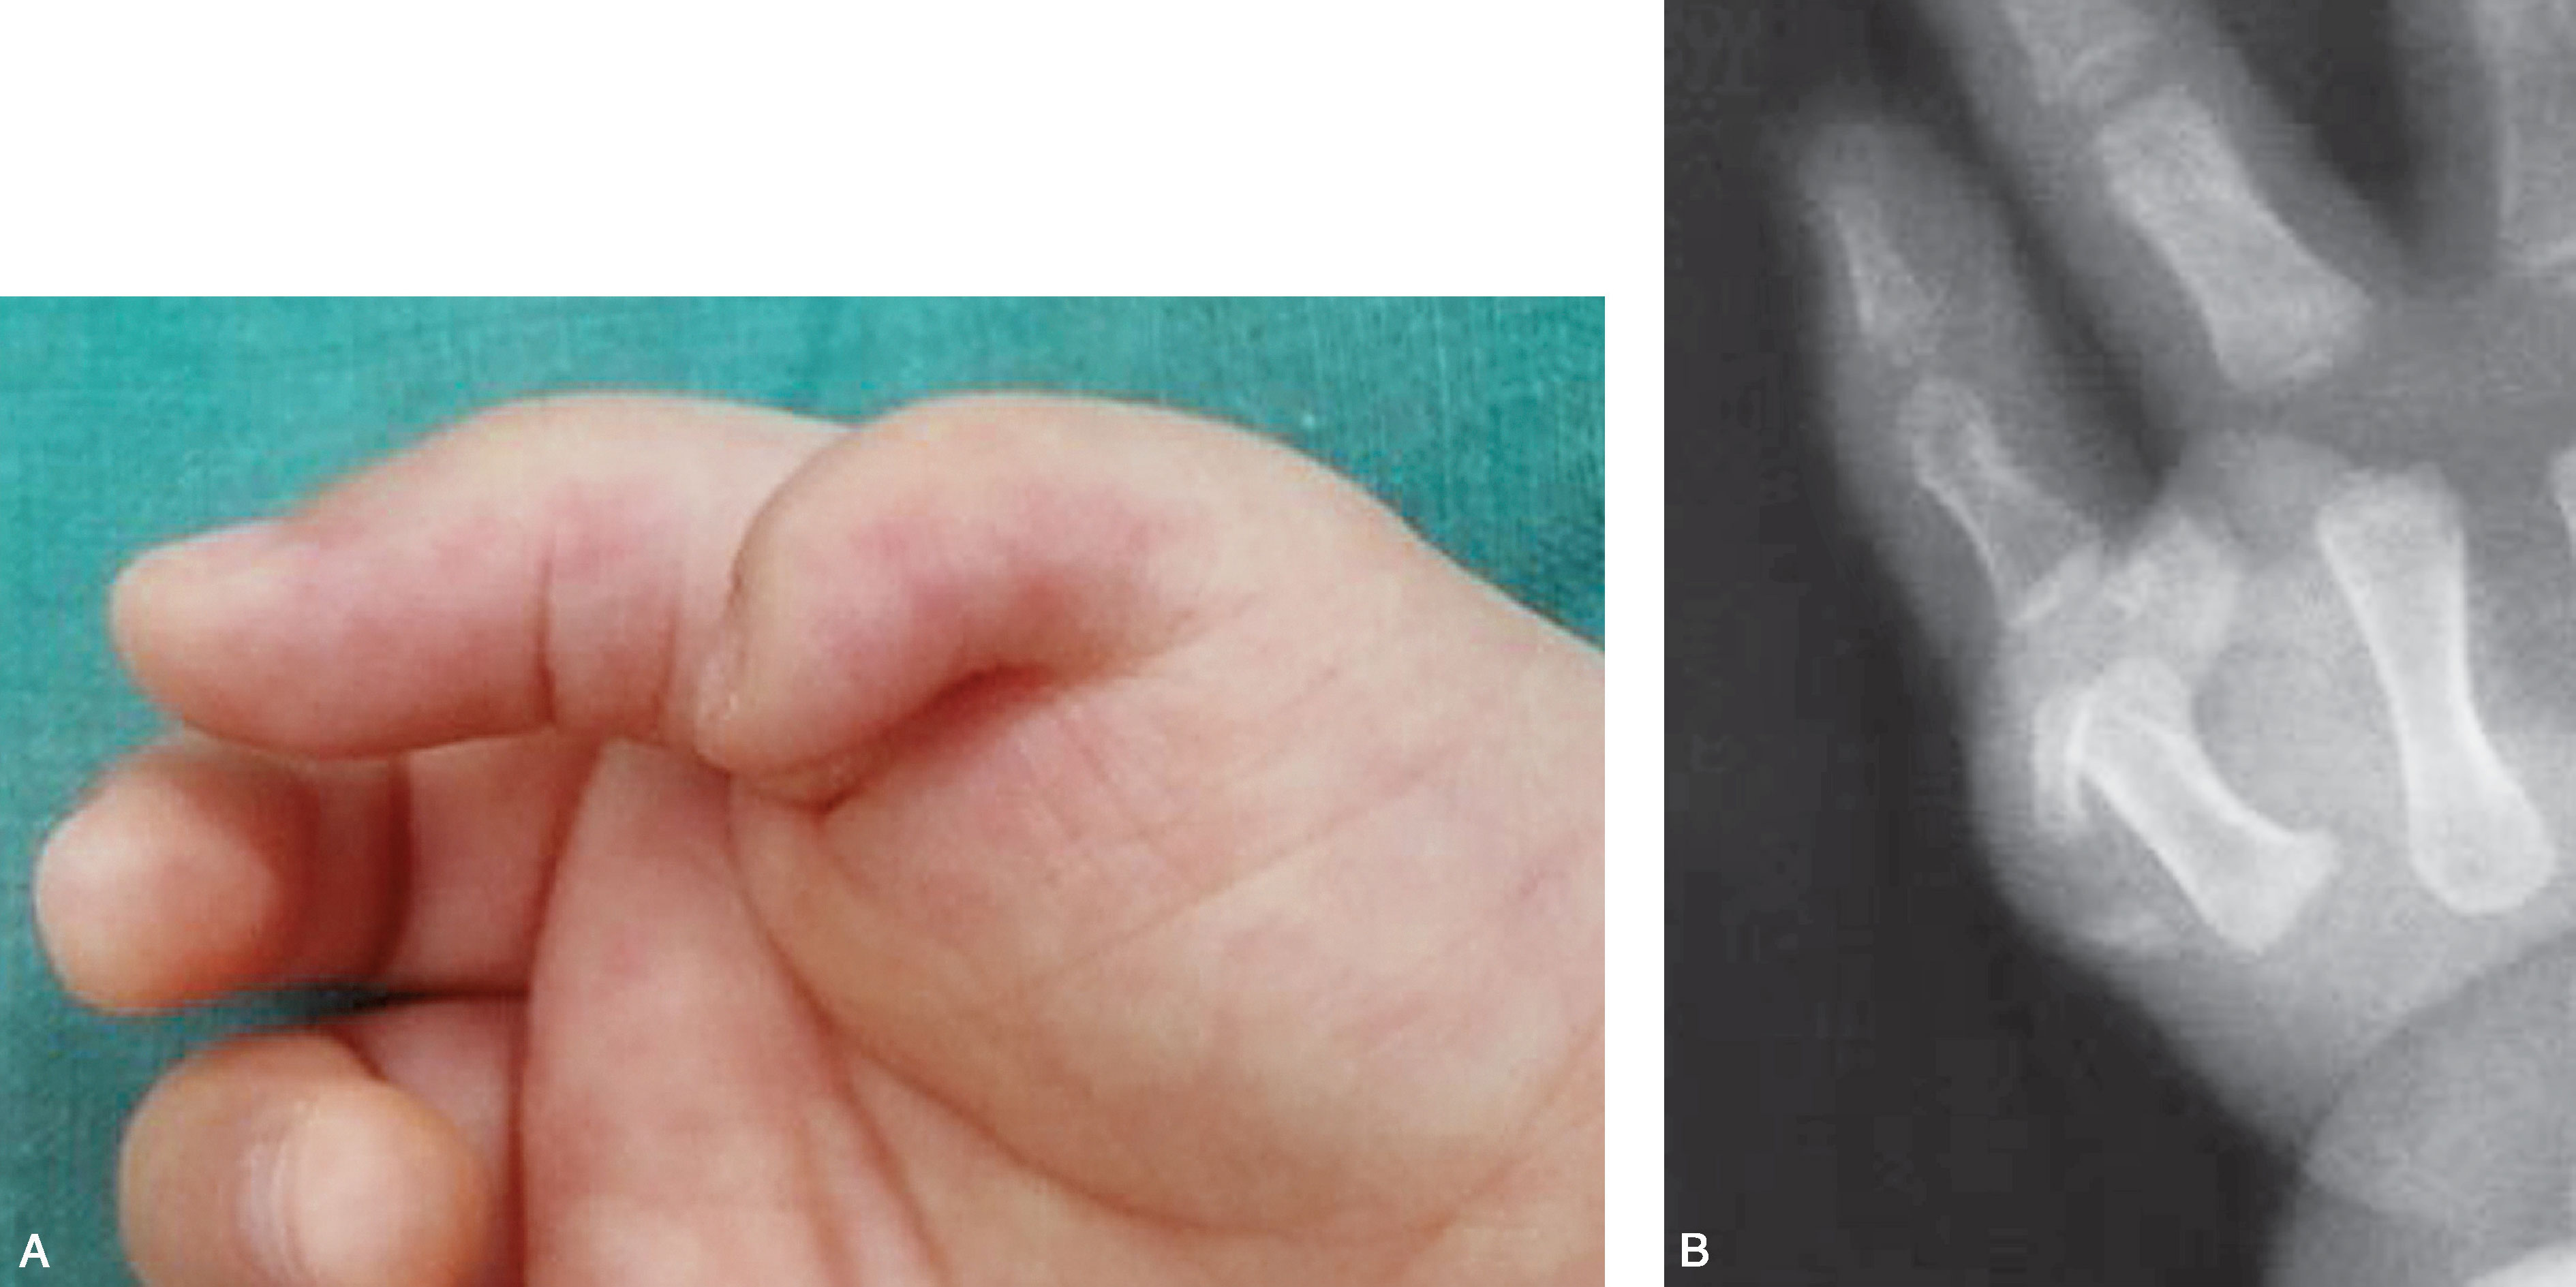

图2-1-18 Ⅲ型病例7

A.右侧多拇指,主、次拇指对称;B.X 线片显示近节指骨分叉位于远端,远节桡、尺侧指骨骨骺对称,近节指骨远端桡、尺侧对称,可选择主、次拇指融合术式,或切除一侧拇指保留另一侧拇指也可